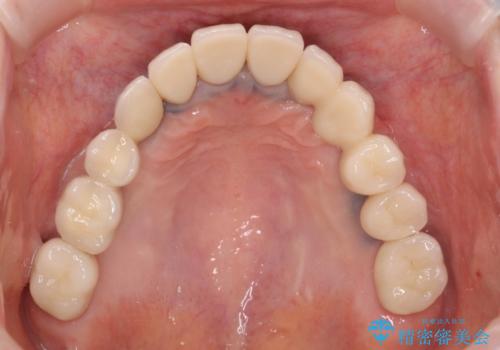

工程数が多かったため治療期間はかかりましたが、しっかりと安定した噛み合わせ、審美的な口腔内環境を達成することができ大変満足していただくことができました。